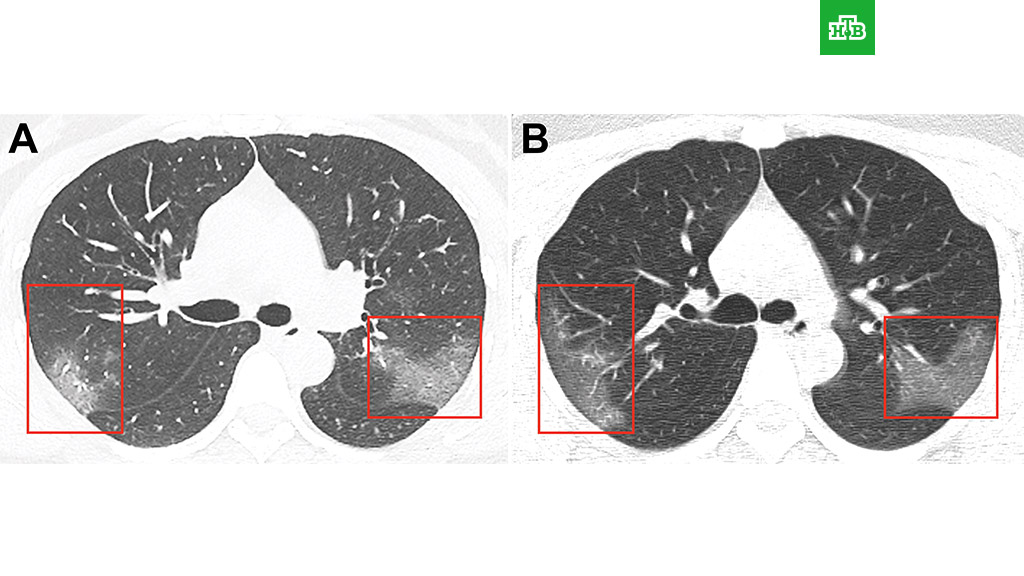

Компьютерная томография грудной клетки выявила в легких женщины множественные периферические помутнения, создающие «эффект матового стекла». Назначенное пациентке лечение в сочетании с ингаляцией с интерфероном не помогло, и снимок, сделанный через три дня, это подтвердил: пораженная область легких расширилась.

Медики отмечают, что двусторонняя непрозрачность легкого является типичным признаком пневмонии, вызванной новым коронавирусом. О дальнейшей судьбе женщины не сообщается.